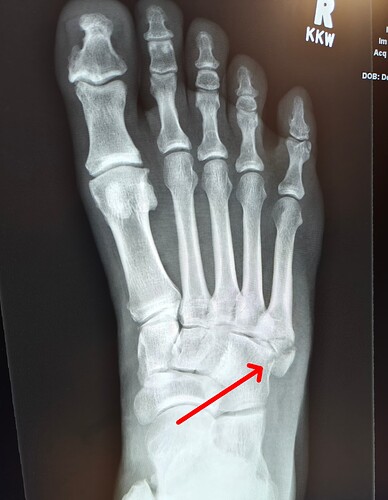

Fack. Sidelined until end of Jan. Had a good run of games going too!

Hope it’s healed up enough to do surfing in Costa Rica in 5-6 weeks time. :flushed_face::grimacing:

Ouch!

Harden up, you’ve got another foot😘